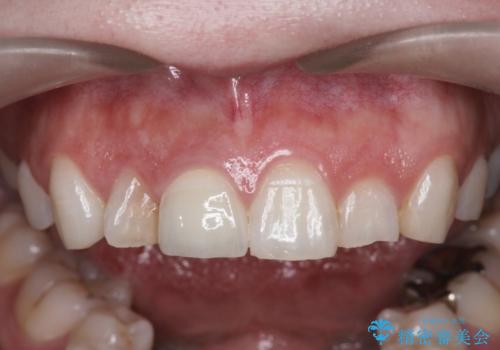

前歯の変色 セラミッククラウンによる審美性の回復

根尖に病変は見られず、根管治療は行わずに仮歯・ジルコニアクラウンを作製、装着することで審美性を回復しました。

- 12.1万円 (仮歯・ジルコニアクラウン)費用は治療当時の料金となります

神経の治療を行った歯は、徐々に変色し審美障害をきたすことはから当院ではセラミッククラウンの装着をお勧めしております。